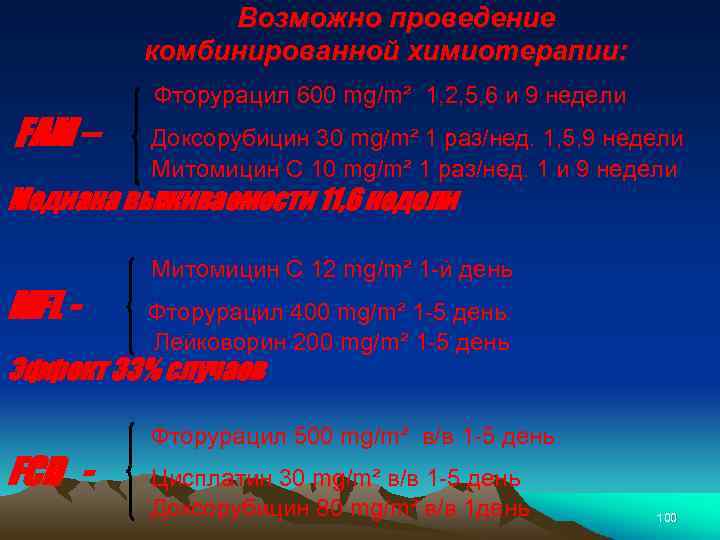

Возможно проведение комбинированной химиотерапии: Фторурацил 600 mg/m² 1, 2, 5, 6 и 9 недели FAM – Доксорубицин 30 mg/m² 1 раз/нед. 1, 5, 9 недели Митомицин С 10 mg/m² 1 раз/нед. 1 и 9 недели Медиана выживаемости 11, 6 недели Митомицин С 12 mg/m² 1 -й день MFL - Фторурацил 400 mg/m² 1 -5 день Лейковорин 200 mg/m² 1 -5 день Эффект 33% случаев FCD - Фторурацил 500 mg/m² в/в 1 -5 день Цисплатин 30 mg/m² в/в 1 -5 день Доксорубицин 80 mg/m² в/в 1 день 100